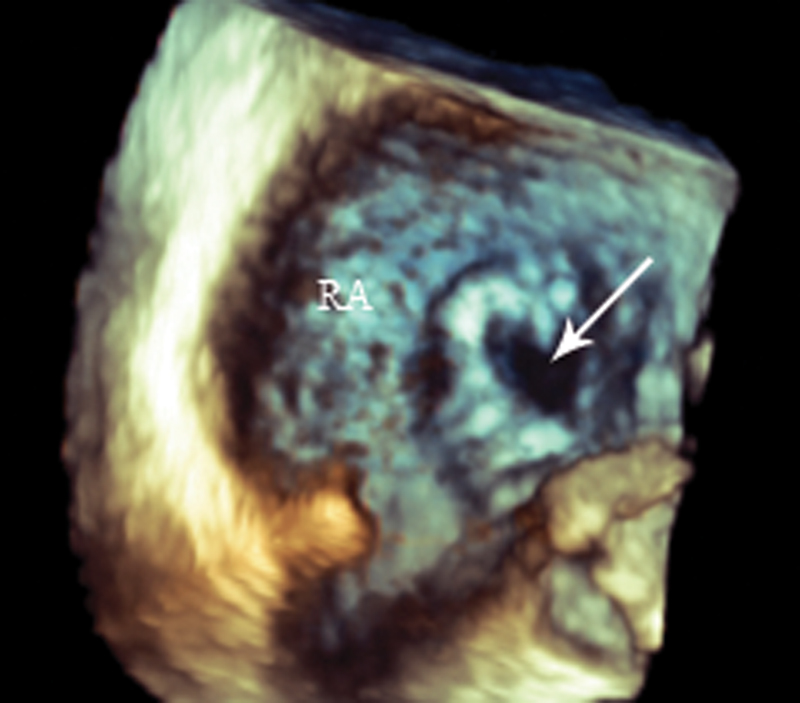

فحوصات تشخيصية لبعض امراض القلب والشرايين التاجية